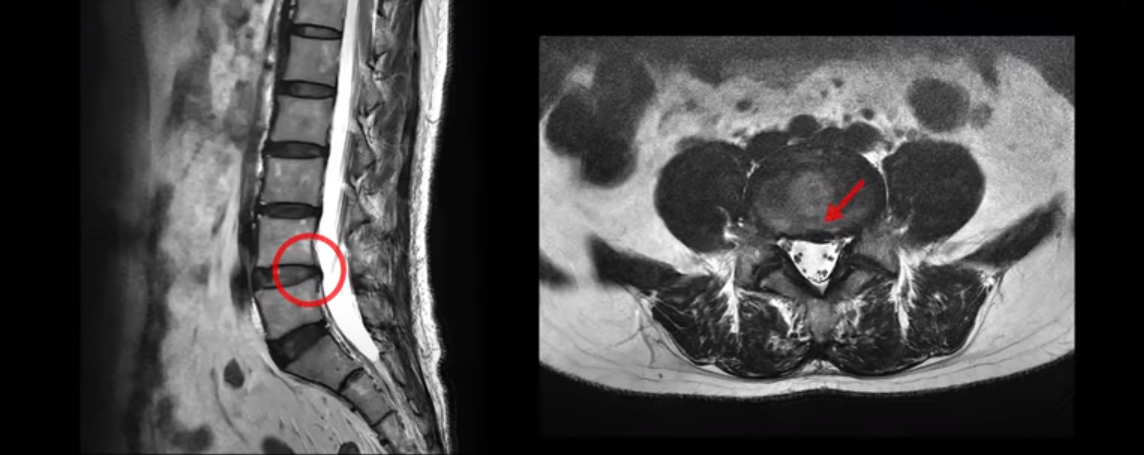

보시다시피 이 환자분의 4, 5번 디스크는 심하지 않습니다.

또한 신경이 나가는 구멍도 넓은 상태로 신경을 누르는 것도 보이지 않습니다.

그런데 이분처럼 디스크 증상이 아닌데도 MRI에 디스크가 조금이라도 보이니까 허리 치료만 받느라 시간을 보내며 고생하시는 분들이 매우 많습니다. 이분의 하지 증상은 양쪽 발 저림 증상입니다. 보통 한쪽 다리가 아픈 디스크로는 설명될 수 없는 증상입니다. 또한 이 분의 등, 허리, 엉치, 허벅지 근육은 전체적으로 엄청나게 뭉쳐있는 상태였습니다.